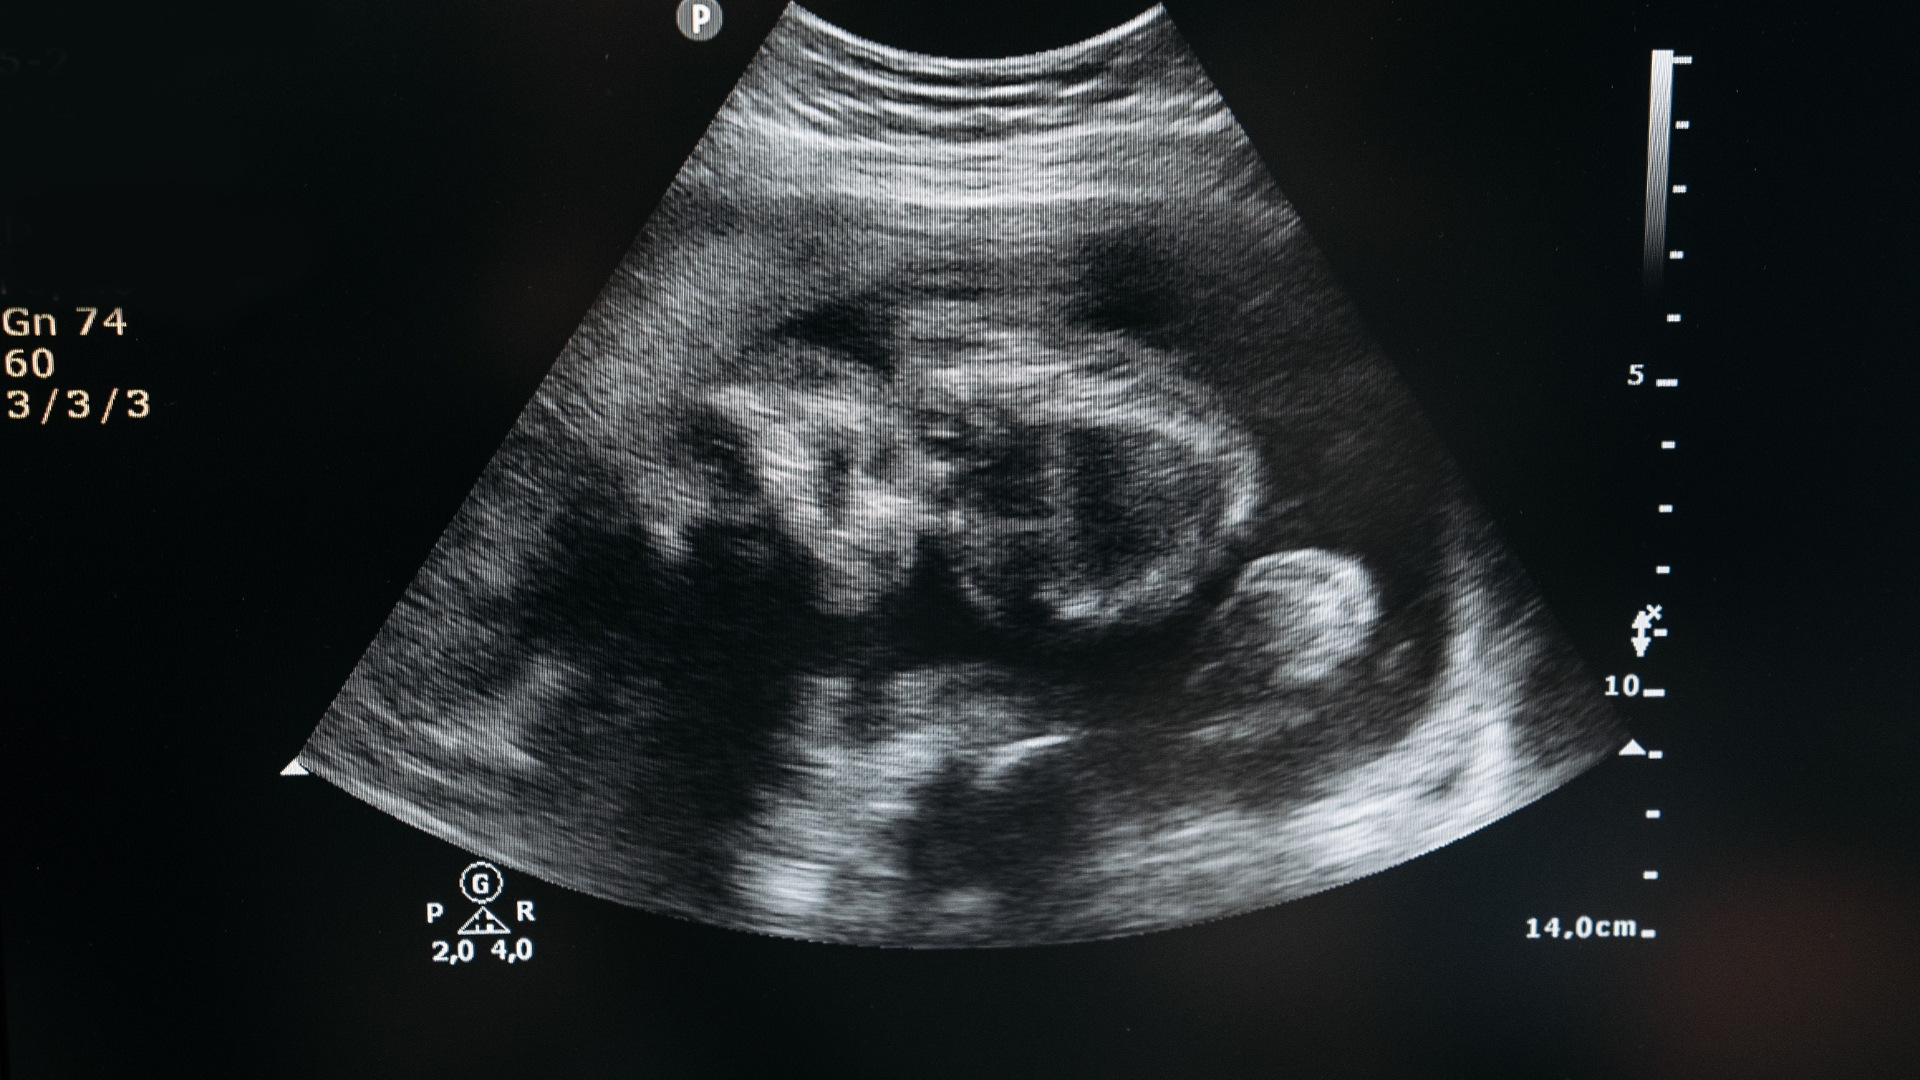

Siêu âm 2D và 3D: Giúp quan sát rõ hình dạng và cấu trúc tử cung, hỗ trợ phân biệt các dạng dị tật thường gặp. Phương pháp này an toàn, dễ thực hiện và được sử dụng đầu tiên trong thăm khám.